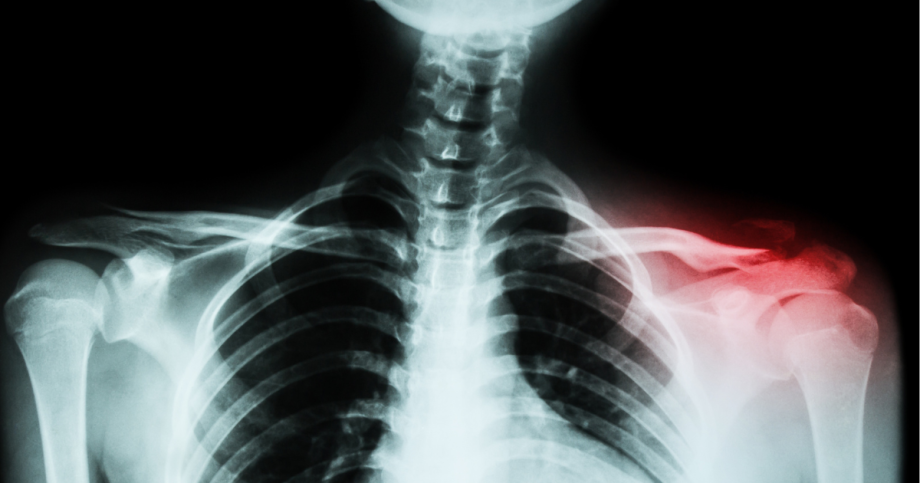

Shoulder pain can significantly impact daily life, and in many cases, surgical intervention may be necessary to restore mobility and reduce discomfort. Procedures like subacromial decompression and distal clavicle resection are commonly performed to relieve pain associated with impingement, arthritis, or rotator cuff injuries.

Subacromial decompression involves removing bone spurs or thickened tissue from the subacromial space; the area between the acromion (part of the shoulder blade) and the rotator cuff tendons. By increasing space in this region, the procedure reduces friction, allowing the rotator cuff to move more freely and alleviating pain caused by impingement.

Distal clavicle resection, often performed alongside subacromial decompression, targets the acromioclavicular (AC) joint. By removing a small portion of the clavicle, this procedure relieves pain caused by arthritis or inflammation in the AC joint.